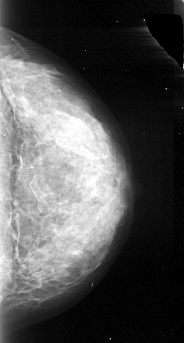

A_1092_1.LEFT_CC

LEFT_CC LINES 4036 PIXELS_PER_LINE 2326 BITS_PER_PIXEL 16 RESOLUTION 42 OVERLAY

FILE: A_1092_1.LEFT_CC.OVERLAY

TOTAL_ABNORMALITIES 1

ABNORMALITY 1

LESION_TYPE CALCIFICATION TYPE PUNCTATE DISTRIBUTION CLUSTERED

ASSESSMENT 4

SUBTLETY 1

PATHOLOGY MALIGNANT

TOTAL_OUTLINES 1

BOUNDARY